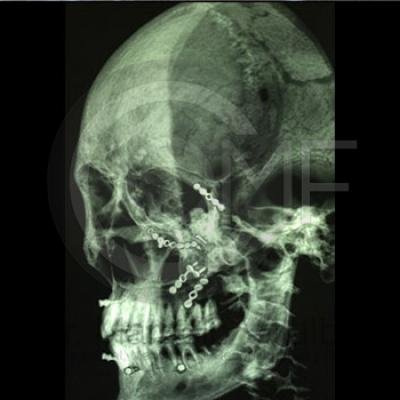

Fractura de Malar